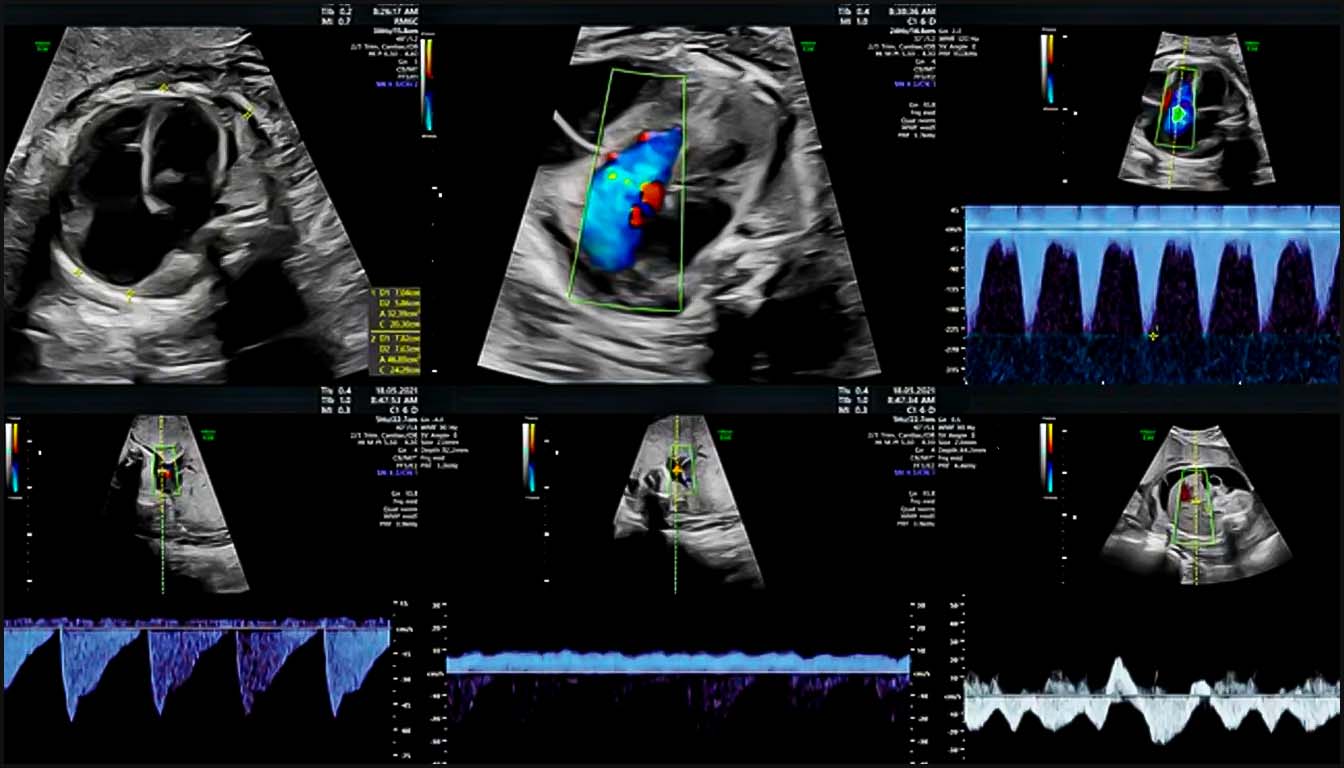

III. Apports du Doppler Couleur et Pulsé

Le Doppler est indispensable pour valider l’anatomie et évaluer la fonction.

• Flux Rétrograde : Un flux inversé (bleu au lieu de rouge ou vice-versa) dans l’isthme aortique ou le canal artériel est un signe de cardiopathie ducto-dépendante, comme une atrésie aortique ou pulmonaire.

• Régurgitations Valvulaires : Une régurgitation tricuspide holosystolique est un marqueur important de CC structurelle et d’aneuploïdie, particulièrement au premier trimestre. Une régurgitation mitrale sévère peut accompagner une sténose aortique critique.

• Flux Veineux : Un flux inversé de l’onde ‘a’ dans le canal d’Arantius (ductus venosus) ou des pulsations dans la veine ombilicale sont des signes de dysfonction diastolique ou d’augmentation de la pression auriculaire droite.

1. Le canal d’Arantius (DV) : L’évaluation par Doppler pulsé du flux veineux est un indicateur puissant de la fonction cardiaque droite. Un flux anormal, caractérisé par une onde ‘a’ inversée ou absente lors de la contraction auriculaire, est associé à un risque accru de CC structurelles, d’aneuploïdies et d’issue de grossesse défavorable. Chez les fœtus euploïdes présentant une CN augmentée, une onde ‘a’ anormale porte la prévalence des malformations cardiaques majeures à environ 15-20 %.

2. La régurgitation tricuspide (TR) : La présence d’un flux rétrograde à travers la valve tricuspide pendant la systole ventriculaire est un signe d’appel majeur. Pour être cliniquement significative au premier trimestre, la TR doit être visible sur au moins la moitié de la systole avec une vélocité supérieure à 60 cm/s. La combinaison d’une CN augmentée, d’une TR et d’un flux anormal dans le DV permet d’identifier jusqu’à 55,5 % des fœtus porteurs d’une CC majeure avec un taux de faux positifs de seulement 8,8 %.

• La coupe des quatre cavités (4C) : Le Doppler couleur permet de visualiser deux flux d’entrée ventriculaires distincts, laminaires et de taille similaire. Il aide à diagnostiquer immédiatement des anomalies comme l’atrésie tricuspide (absence de flux à droite) ou les canaux atrioventriculaires (CAV), souvent identifiables par un flux unique en forme de “Y”.

• La coupe des trois vaisseaux et de la trachée (3VT) : Cette vue est cruciale pour évaluer les voies d’éjection et les arcs vasculaires. Normalement, l’isthme aortique et le canal artériel convergent à gauche de la trachée pour former un signe en “V” avec un flux antégrade et non turbulent. Le Doppler couleur facilite la détection précoce de la transposition des gros vaisseaux (TGV), où les vaisseaux apparaissent parallèles, et des anomalies de l’arc comme l’artère aortique droite, signalée par un signe en “U” entourant la trachée.

L’ajout du Doppler couleur à l’évaluation de la 4C et des voies d’éjection augmente significativement la sensibilité du dépistage, passant d’environ 42 % à 78 % dans les populations à bas risque.

• Le Score de Profil Cardiovasculaire (CVP) : Ce score sur 10 points intègre des marqueurs Doppler artériels (artère ombilicale) et veineux (veine ombilicale, canal d’Arantius) pour évaluer la sévérité d’une insuffisance cardiaque. Un score CVP $\le$ 7 est prédictif d’une mortalité périnatale accrue.

• Arythmies : Le Doppler simultané de la veine cave supérieure et de l’aorte permet de documenter la relation entre les contractions auriculaires et ventriculaires, facilitant le diagnostic précis des tachycardies (ex: flutter auriculaire) ou des blocs auriculoventriculaires.

1. Analyse de la fonction diastolique et pressions veineuses

La fonction diastolique fœtale est principalement évaluée par le Doppler pulsé au niveau des valves auriculo-ventriculaires (mitrale et tricuspide). Normalement, le flux présente un aspect biphasique avec une onde E (remplissage passif) et une onde A (contraction auriculaire). Une inversion du rapport E/A ou un flux monophasique sont des signes de réduction de la compliance ventriculaire ou d’augmentation des pressions de remplissage.

Le Doppler veineux est le reflet direct des pressions dans l’oreillette droite. L’analyse du canal d’Arantius (DV) est ici cruciale : un flux antégrade est normal, tandis qu’une onde ‘a’ absente ou inversée indique une augmentation de la pression veineuse centrale et une dysfonction cardiaque droite. Si la situation s’aggrave, ces anomalies de pression se transmettent à la veine ombilicale, où l’on observe alors des pulsations anormales, signe pré-terminal de défaillance cardiaque.

1. Évaluation du rythme et de la conduction

Le Doppler est l’outil de référence pour diagnostiquer les arythmies fœtales en l’absence d’ECG direct. Le Doppler pulsé simultané de la veine cave supérieure et de l’aorte permet de documenter la relation temporelle entre les événements auriculaires (onde ‘a’ de la veine) et ventriculaires (flux aortique). Cette technique permet de différencier :

1. Les tachycardies supraventriculaires (SVT) par réentrée (conduction 1:1).

2. Le flutter auriculaire, caractérisé par une fréquence auriculaire très élevée (jusqu’à 400 bpm) avec un bloc auriculo-ventriculaire variable.

3. Le bloc auriculo-ventriculaire (BAV) complet, où l’on observe une dissociation totale entre les contractions auriculaires et ventriculaires, souvent associé à des maladies auto-immunes maternelles.